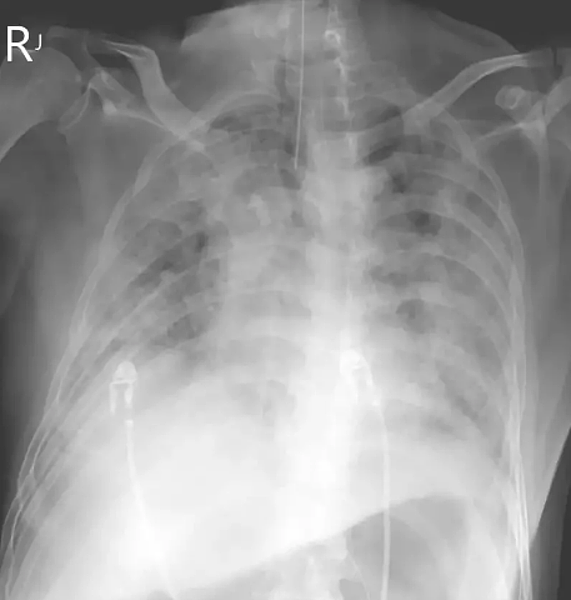

中國大陸新冠疫情嚴峻,台北市立聯合醫院陽明院區胸腔內科主治醫師蘇一峰,昨在個人臉書PO出一張「大白肺」胸部X光片。他表示,這是一名60歲台商大白肺(肺炎重症)了,返台三天自己篩檢確診,但沒有第一時間就醫,等到四、五天後不舒服才拿藥吃,到院治療給抗病毒藥物,但還是擋不住病情進展,現在插管病危。

台北醫學大學附設醫院胸期內科主治醫師周百謙說,「大白肺」是肺部遭細菌或病毒嚴重感染引起損傷,原先肺部充滿空氣的地方,已積滿了發炎物質,X光無法穿透。此現象常出現在肺部感染重症或呼吸衰竭病人,有別於無症狀、輕症感染,肺部X光片僅會出現浸潤、毛玻璃等現象,不會整個變白,這樣的情形,不只是感染新冠病毒才會發生,而是肺部遭到任何細菌或病毒感染重症都有可能發生。

「現在努力拚看看能不能救他的命」,蘇一峰說,還有點搞不清楚病人是在哪裡感染確診,指揮中心應該驗看看這名患者的病毒基因定序,看看是哪一種。蘇曾表示,大白肺(肺炎重症)死亡率高達五成以上,年輕人才有機會活下來,「呼吸器、藥物、醫護人員,缺少一個絕對死,就算活下來也會遺留下肺纖維化」,肺纖維化愈早期治療效果愈好。